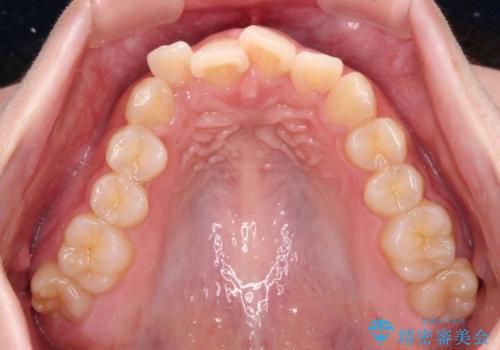

口元の突出感は強くなかったため非抜歯矯正での対応となりますが、捻転を改善する際に上顎前歯が前突する可能性があったため、上顎臼歯部にアンカースクリューを使用して、歯列が前方に転位しないようにすることとしました。

また舌のトレーニングを行うことで、上顎前歯の突出予防や上下前歯に隙間ができなくなるようにしました。

ワイヤー矯正でもインビザラインでも対応可能でしたが、上顎歯列が前方位であるときには、ワイヤー矯正の方がより良い仕上がりとなる可能性が高いため、ワイヤー矯正をおすすめいたしました。